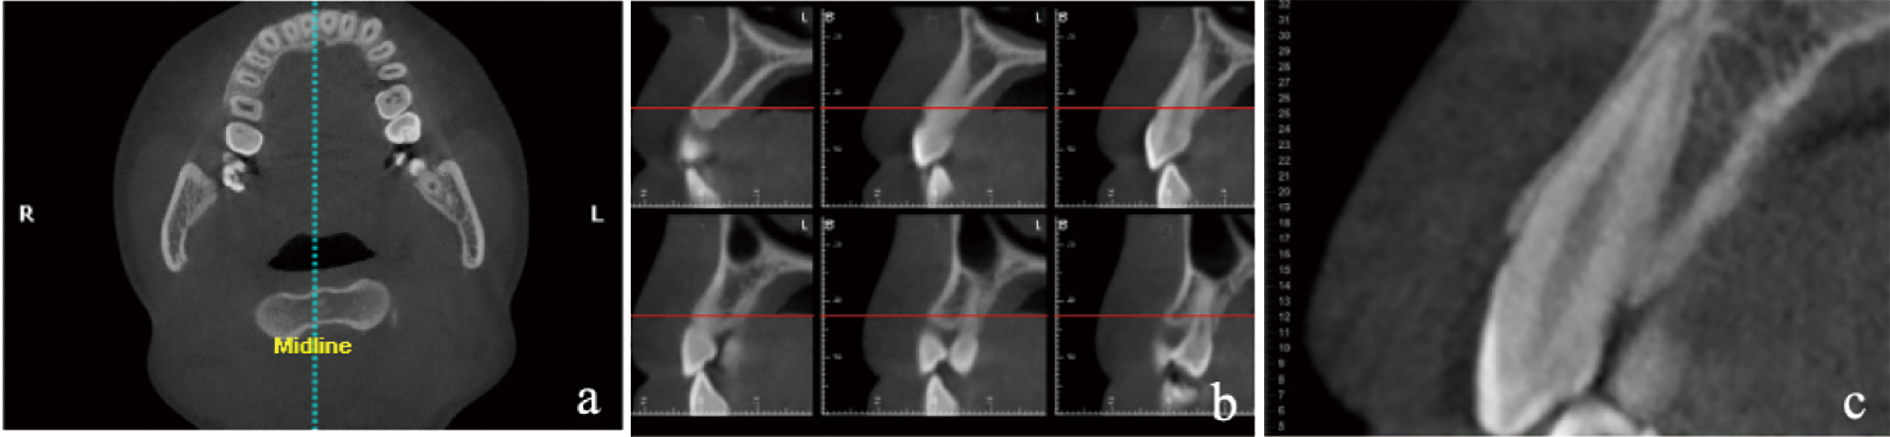

Han SB, Fan XF, Wang S, et al. Dehiscence and fenestration of skeletal Class Ⅲ malocclusions with different vertical growth patterns in the anterior region: A cone-beam computed tomography study[J]. Am J Orthod Dentofacial Orthop, 2024, 165(4): 423-433.

Lei C, Yu Q, Wu D, et al. Comparison of alveolar bone width and sagittal tooth angulation of maxillary central incisors in Class Ⅰ and Class Ⅲ canine relationships: A retrospective study using CBCT[J]. BMC Oral Health, 2022, 22(1): 303.

Rodrigues DM, Petersen RL, Montez C, et al. The relationship between tomographic sagittal root position of maxillary anterior teeth and the bone housing[J]. J Prosthet Dent, 2023, 130(5): 705-714.

Evangelista K, Vasconcelos KD, Bumann A, et al. Dehiscence and fenestration in patients with Class Ⅰ and Class Ⅱ Division 1 malocclusion assessed with cone-beam computed tomography[J]. Am J Orthod Dentofacial Orthop, 2010, 138(2): 133.e1-133.e7;discussion 133-135.